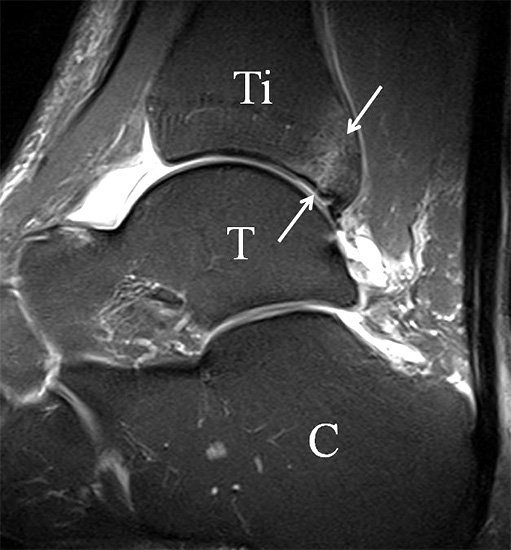

b. T2 fs axial. Infraktion des hinteren Volkmann‘schen Dreiecks (schmale, weiße Pfeile). Hier inserierende, intakte, hintere Syndesmose (breite, weiße Pfeile).

Abbildung 18b

Das Ligamentum tibiofibulare posterius (hintere Syndesmose) verläuft flacher und geht nach kranial in das Ligamentum tibiofibulare interosseus und nach kaudal in das Ligamentum intermalleolare posterius über. Letzteres bildet ein artikuläres Labrum zwischen Trochlea und Talus 9.

Da also die hintere Syndesmose an der posterioren Tibia inseriert, entspricht eine Fraktur oder Infraktion des hinteren Volkmann`schen Dreiecks funktionell einem knöchernen Ausriss des Ligamentum tibiofibulare posterius (Abb. 18 a und b). Aufgrund der Koinzidenz von Syndesmosenläsionen mit Innenbandverletzungen ist bei der Beurteilung gesondert auf solche zu achten.